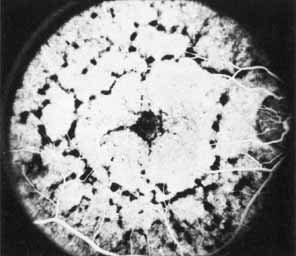

Although there is no reported genetic heterogeneity, there is wide phenotypic variation within the disorder. The major finding within the macula is a classic radial cystic maculopathy. Although retinal signs have been described in infants as young as 3 months, foveal schisis may be difficult to detect, leading to underdiagnosis. The diagnosis is usually not made until the affected male reaches school age (4 to 8 years of age) and encounters visual problems secondary to foveal involvement. Typical foveal schisis findings have been reported in 68% to 100% of eyes within various series.37,38 Foveal schisis is the only finding in about half the cases. It is characterized by the presence of radiate perifoveal microcysts located in the nerve fiber layer (Fig. 1) with radiate plications of the overlying internal limiting membrane that are seen especially well on monochromatic (red-free) photography (Fig. 2). The microcystoid change may slowly progress to form a macular cyst or hole. Foveal schisis has been reported in association with Goldmann-Favre vitreotapetoretinal dystrophy and rarely may be seen in rod-cone dystrophy or as an autosomal dominant or recessive condition.39–43